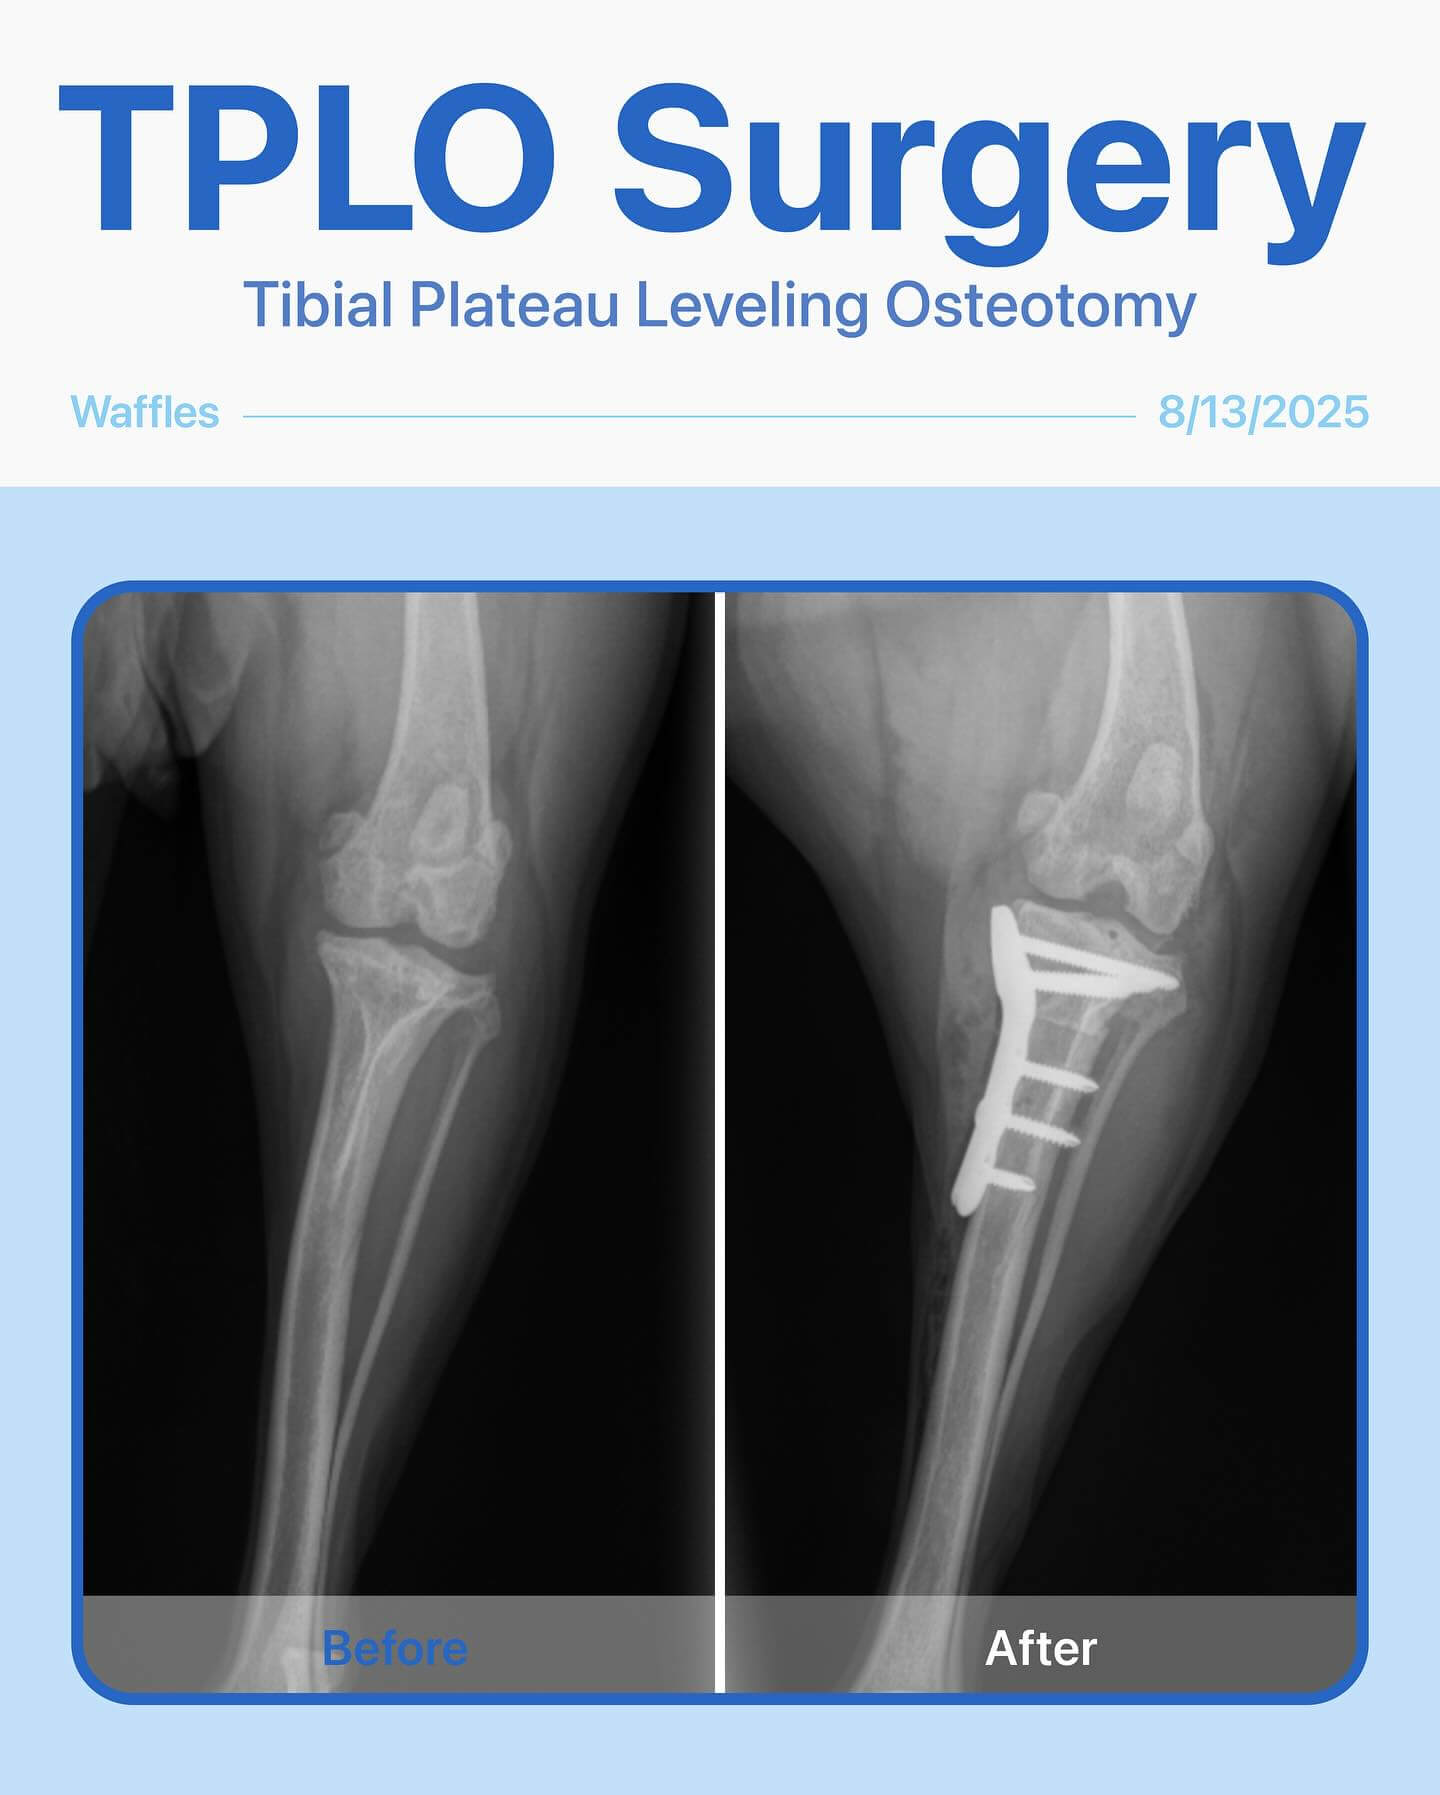

Before & After – TPLO Surgery for Waffle!

Waffle, our sweet 4-year-old girl, came in with a limp in her back left leg and low energy that had been bothering her for a few months. After a thorough physical exam and radiographs, we diagnosed her with a cranial cruciate ligament (CCL) rupture—a common injury in dogs that causes pain, instability, and difficulty walking.

To restore her mobility and relieve pain, Waffle underwent TPLO (Tibial Plateau Leveling Osteotomy) surgery. The procedure went smoothly, and Waffle is on her way to a full recovery!